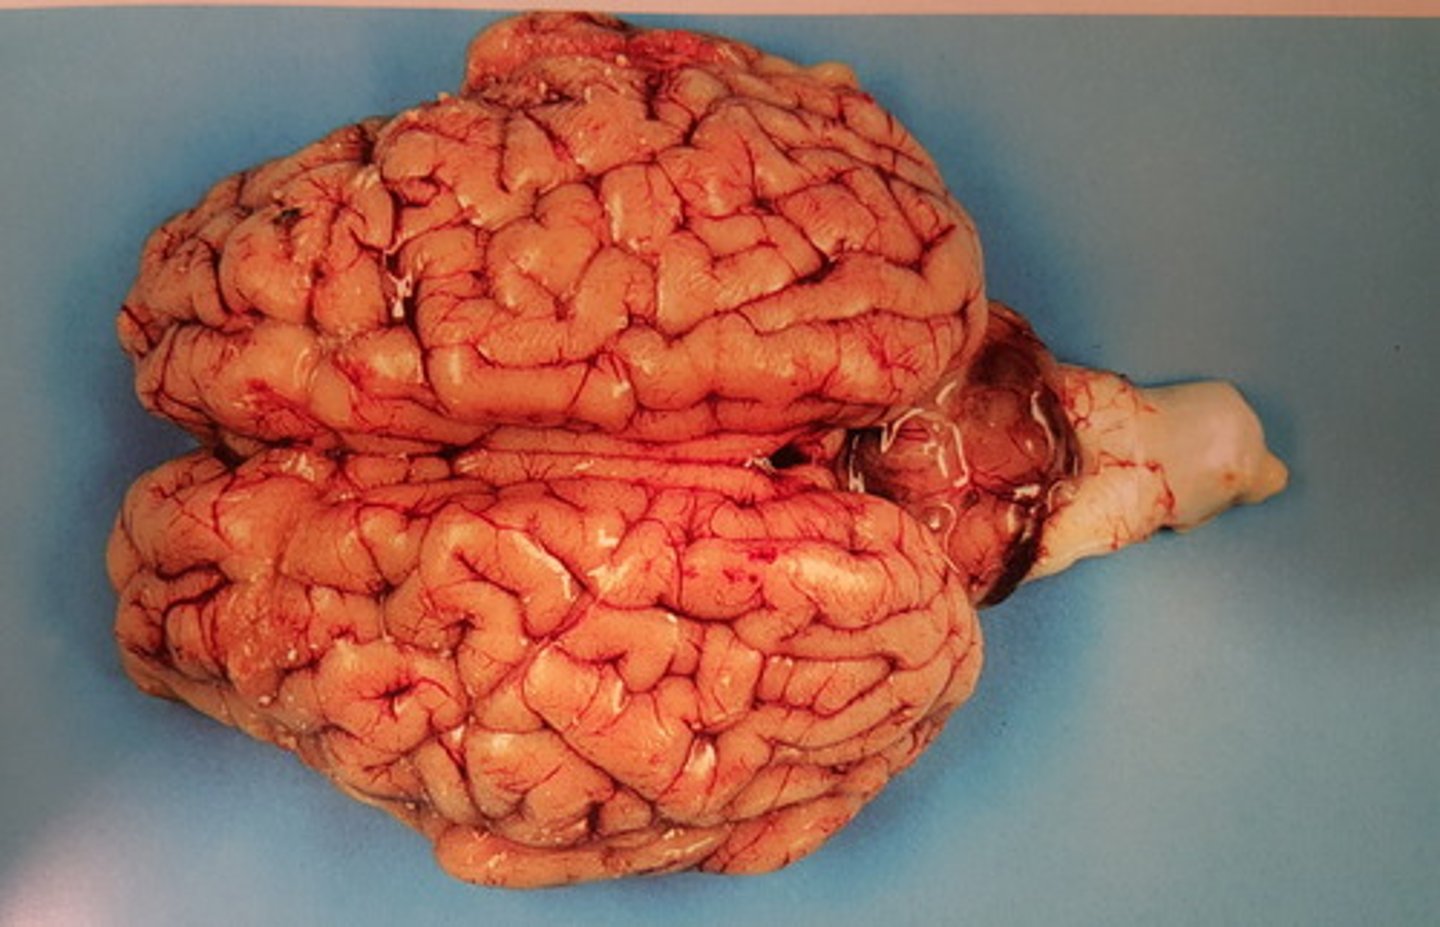

kronisk dissemineret granulomatøs meningitis Infektion med mycobacterium bovis

Rygmarv med hinder fra okse. Patoanatomisk diagnose? Ætiologi?

kronisk dissemineret granulomatøs encephalitis og meningitis. Infektion med mycobacterium bovis

Hjerne med hinde fra okse. Patoanatomisk diagnose? Ætiologi?